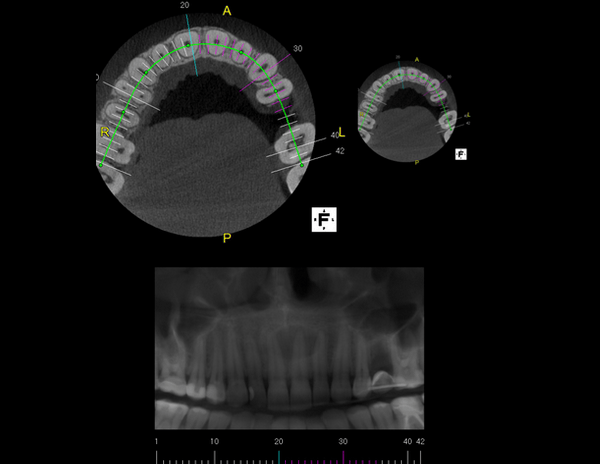

A Tomografia Computadorizada pela técnica do feixe cônico/cone beam (CBCT) introduziu um novo conceito de tomografia computadorizada na região bucomaxilofacial, que por meio da rápida aquisição volumétrica produz imagens com altíssimo grau de definição e fidelidade, além da redução na dose total de radiação emitida ao paciente.

Além disso, ocorre a minimização dos artefatos de imagem em relação à TC médica, o que torna possível a realização de imagens com qualidade diagnóstica e precisão sub-milimétrica, mesmo na presença de estruturas metálicas (restaurações, pinos/núcleos, aparelhos ortodônticos).